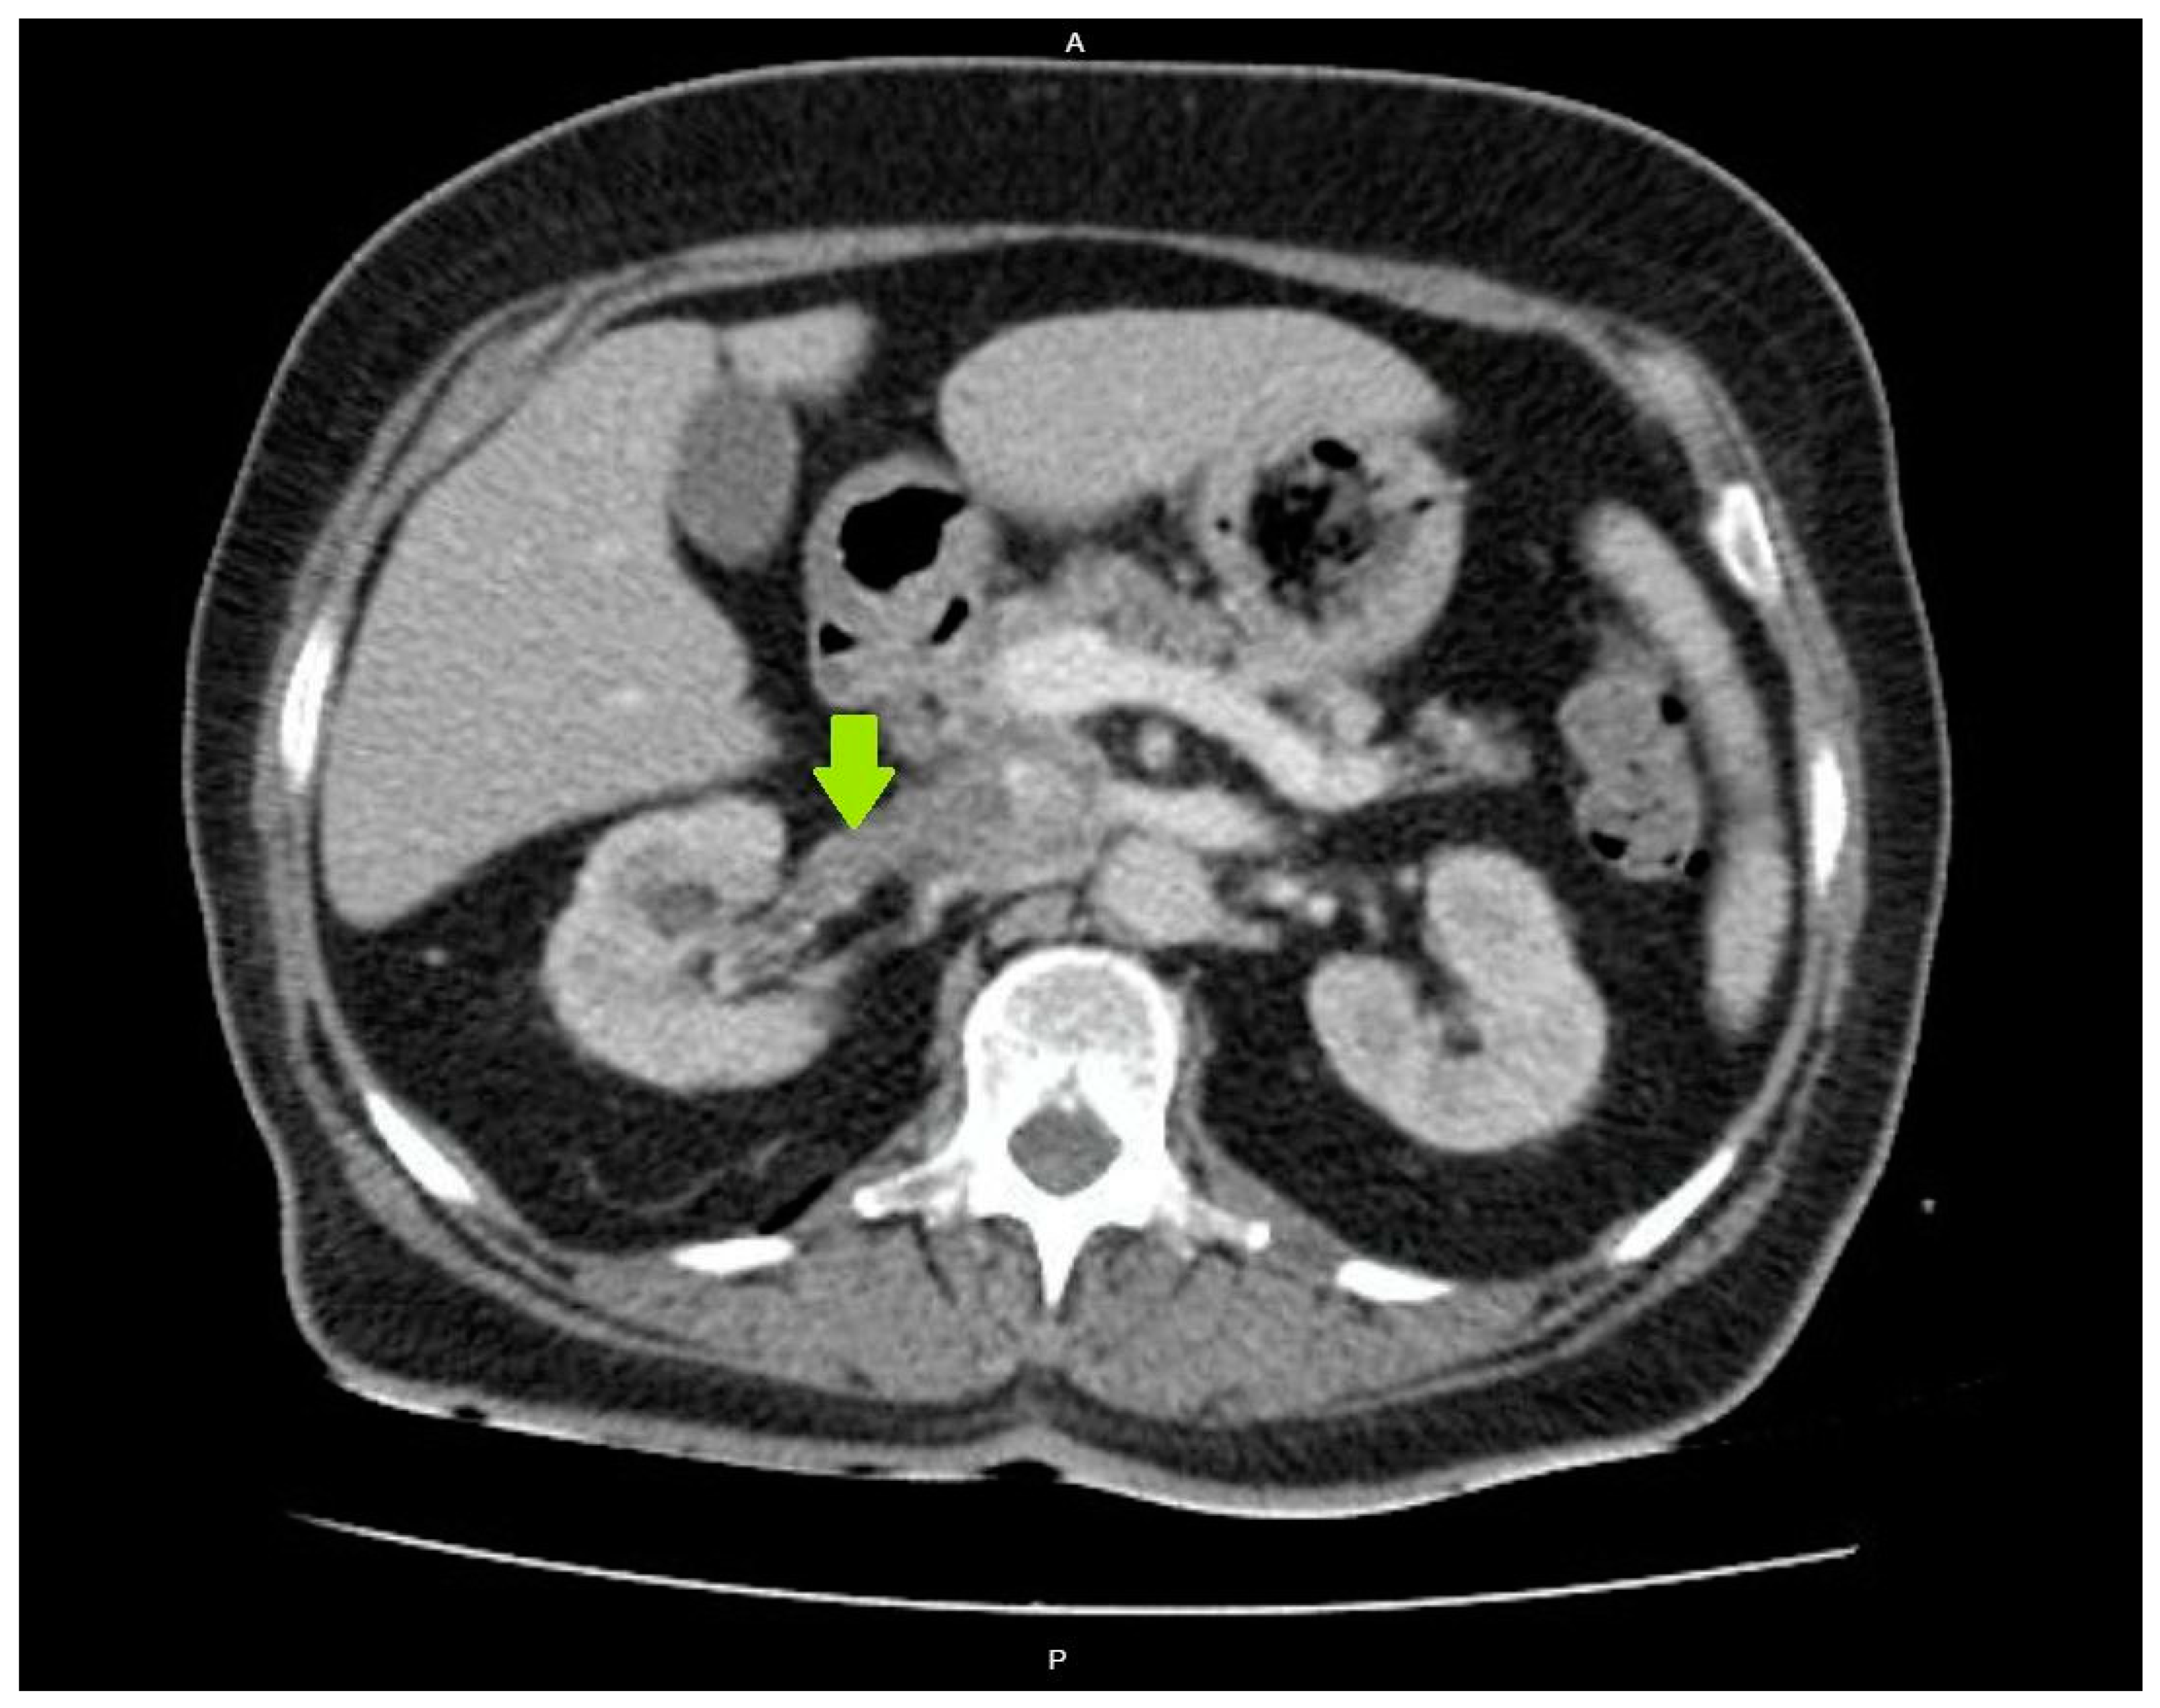

2. Case Presentation